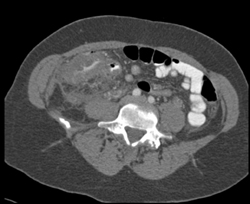

Cecal Cancer